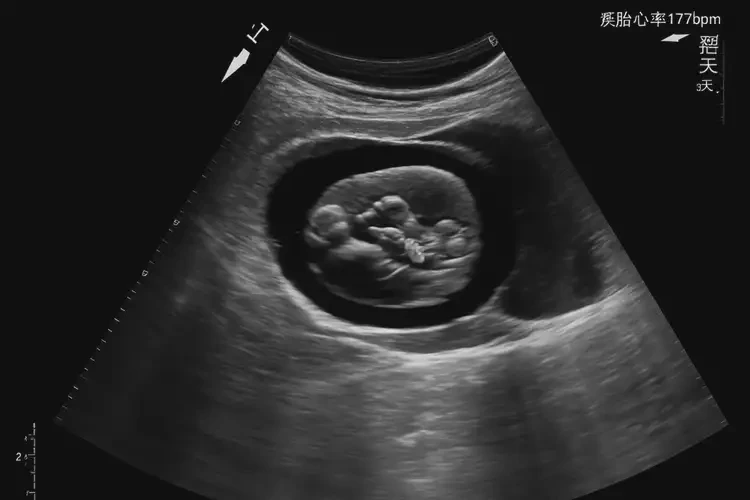

孕5周3天胎心率177還能保住嗎

胎心率177次/分鐘在孕5周3天的情況下,屬于正常范圍,胎兒通常可以保住。

在孕早期,胎心率通常較快,正常范圍為120-180次/分鐘。孕5周3天的胎心率177次/分鐘雖然接近上限,但并未超出正常范圍。以下是詳細(xì)分析:

孕5周3天胎心率177還能保住嗎(圖1)